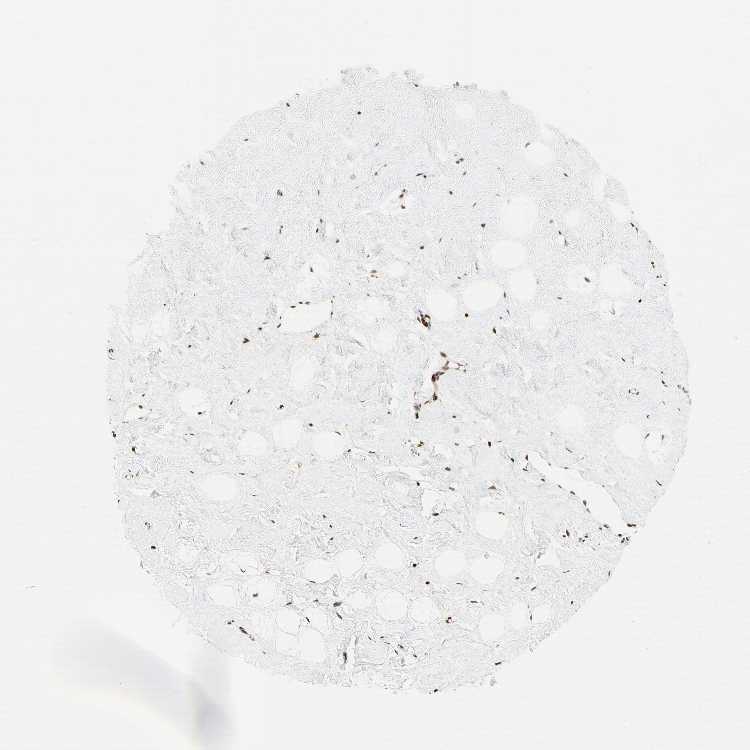

BREAST - Antibody stainingi

Antibody staining in the annotated cell types in the current human tissue is reported as not detected, low, medium, or high, based on conventional immunohistochemistry profiling in selected tissues. This score is based on the combination of the staining intensity and fraction of stained cells.

Each image is clickable and will lead to virtual microscopy that enables deeper exploration of all samples and also displays staining intensity scores, fraction scores and subcellular localization as well as patient and tissue information for each sample.

Antibody HPA008834

Adipocytes Medium

Glandular cells Medium

Myoepithelial cells Medium